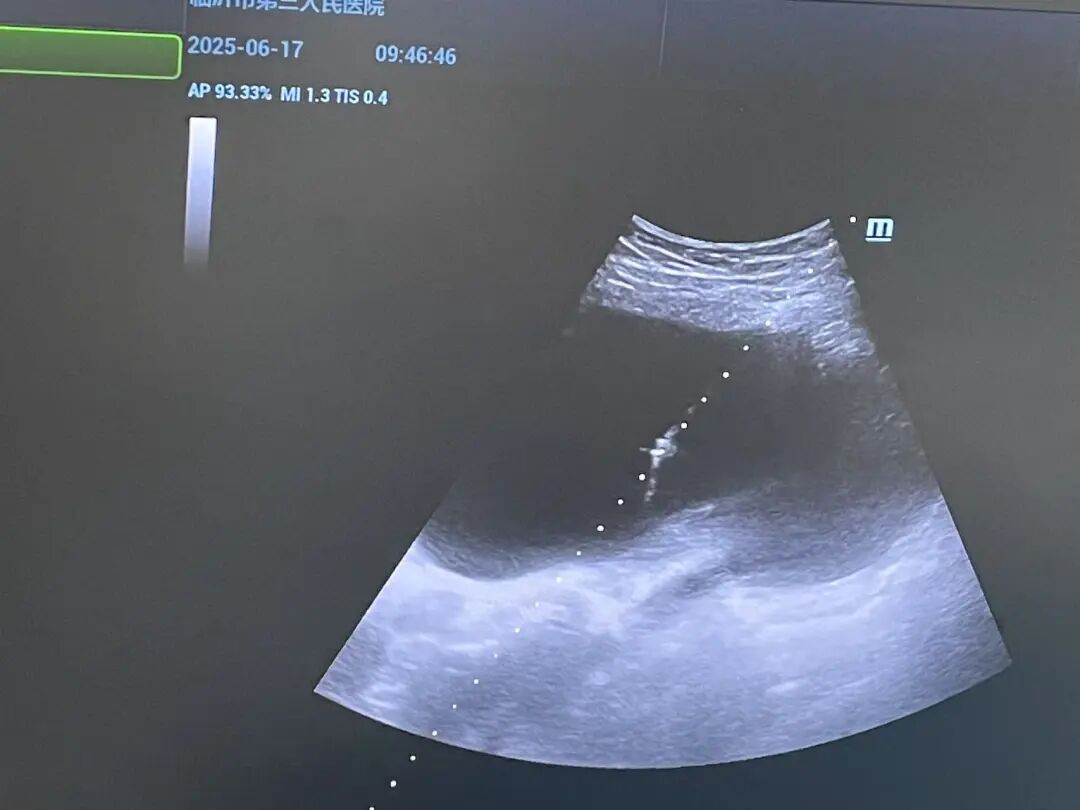

6月17日,我院介入超声团队成功运用超声引导下穿刺引流硬化术,为一名患有右侧腹盆腔巨大囊肿(30cmx20cm)的患者解除了病痛,再次展现了介入超声技术的强大优势。 病例速览 患者行腰椎CT检查时发现腹腔内囊性占位来院就诊。 微创出击 介入超声团队评估后,决定采用介入超声微创治疗: 1.精准穿刺:在超声实时引导下,精确定位,避开危险区域。 2.高效引流:仅通过一根细针,成功抽出囊液1210毫升,囊肿显著缩小,患者压迫感即刻缓解。 3.关键硬化:注入硬化剂破坏囊壁分泌功能,有效预防复发(术中显示硬化良好)。 手术创伤极小(仅一个针眼),术后患者安返病房,恢复顺利。